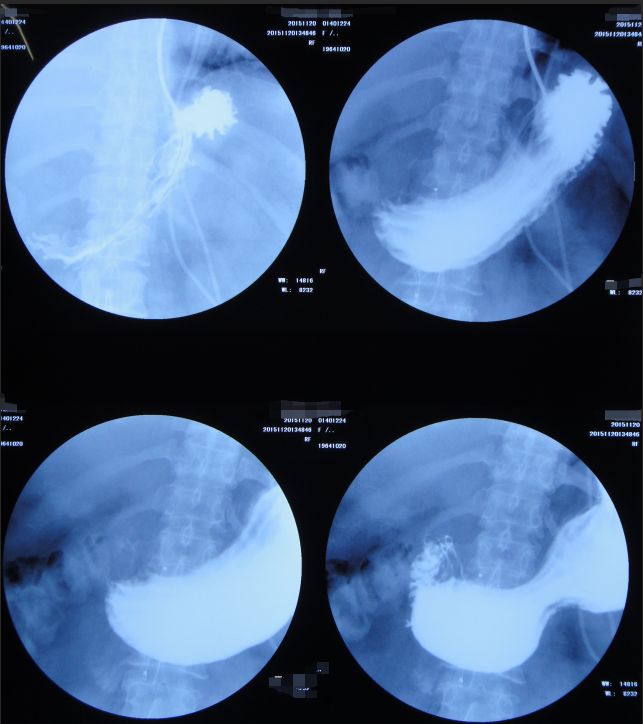

2015年10月29日患者病情进一步恶化,神志朦胧,精神差,呼吸急促,心率132次/分,呼吸36次/分,血压95/59mmHg,血氧饱和度98%。请消化内科急会诊:考虑患者目前病情严重,当日急诊进行经内镜逆行性胰胆管造影术(ERCP)手术(图33)。

![]()

图33:2015年10月29日患者接受急诊ERCP